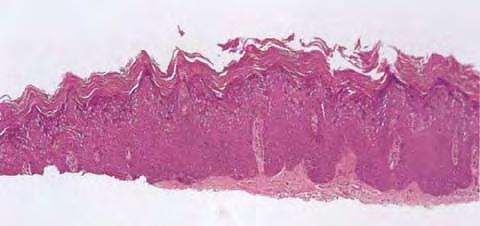

Verruca plana = الثؤلول المسطح